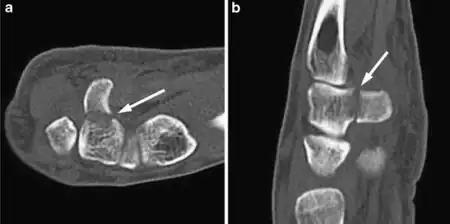

Hamate fracture

| Fracture through the hook of the hamate | |

Hamate fracture is a break of the hamate bone in the wrist. Symptoms include pain in the front of the wrist in line with the little finger.[1] It is made worse by gripping an object.[1] Complications may include injury to the ulnar nerve and clotting of the ulnar artery.[1]

The cause is typically injury during racket sports, baseball, or golf or a fall onto the hand.[1][2] Types include hook (most common) and body (proximal pole, medial tuberosity, sagittal oblique, and dorsal coronal).[1] Diagnosis is typically by X-rays, but may require special views such as a carpal tunnel or supinated oblique view; or a CT scan.[1]